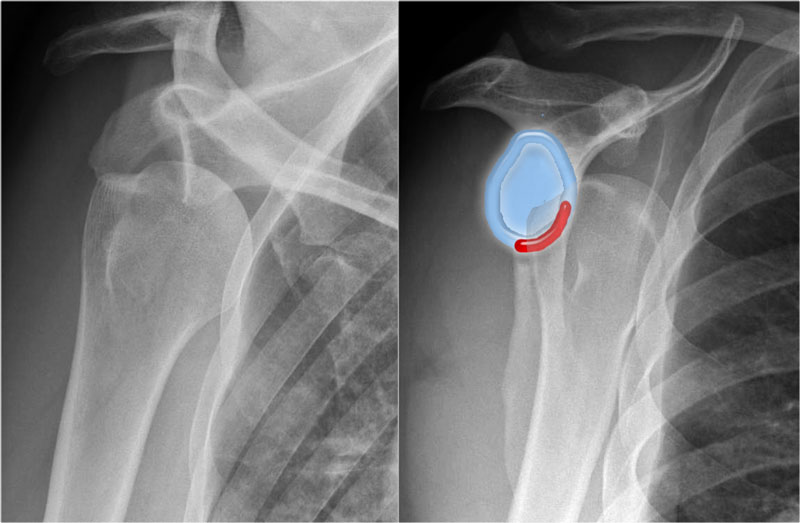

Trật khớp ra sau ít gặp và dễ bị bỏ sót, do mức độ di lệch ít hơn so với trật khớp ra trước.

Trên phim thẳng (AP), chỏm xương trông bất thường do xoay trong.

Trên phim chếch qua xương bả vai (transscapular-Y), chỏm xương cánh tay bị di lệch ra sau.

Đôi khi mức độ di lệch khó đánh giá, đặc biệt khi phim chếch qua xương bả vai bị xoay nhẹ.

Đôi khi phim chụp tư thế nách có thể hữu ích, nhưng khi còn nghi ngờ nên chỉ định chụp CT.

Hình ảnh của một bệnh nhân khác bị trật khớp ra sau.

Lưu ý khoảng cách giữa chỏm xương cánh tay và ổ chảo trên phim thẳng (AP) rộng bất thường.

Trật khớp vai ra sau ít gặp và không rõ ràng trên phim X-quang như trật khớp ra trước.

Khoảng một nửa số trường hợp trật khớp vai ra sau không được chẩn đoán ngay lần khám đầu tiên, do mức độ nghi ngờ lâm sàng thấp và hình ảnh học chưa đầy đủ.

Trật khớp ra sau chiếm 2-4% tổng số các trường hợp trật khớp vai.

Trật khớp ra sau có liên quan đến cơn động kinh, chấn thương năng lượng cao, điện giật và liệu pháp sốc điện.